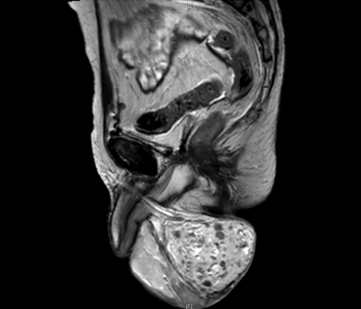

A 55-year-old male diagnosed with prostate cancer in 2010 and underwent radical prostatectomy followed by salvage radiation therapy to the prostatic fossa. He was found to have bone metastasis and since had been treated with hormonal therapy, enzalutamide, abiraterone, radium-223, and taxotere. In April 2016, the patients PSA was >1500 ng/dl. In August 2016, the patient,s was found to have bone marrow involvement with anemia (hemoglobin 6.1 g/dL) and thrombocytopenia (platelets 32x103/ul). In November 2016, the patient began complaining of scrotal pain. Physical examination demonstrated an enlarged scrotum with palpable mass and magnetic resonance imaging (MRI) scan revealed a right testicular hydrocele containing multiple enhancing nodules (Figure 1) (Figure 2) (Figure 3) (Figure 4). At last follow-up on November 10, 2016, the patient continued to have scrotal pain, and required transfusions for anemia and thrombocytopenia and is currently being treated with carboplatin and cabazitaxel.

Cursor on image to zoom/Click text to open image

Figure 1: T2 magnetic resonance imaging scan sagittal view showing right testicle with multiple enhancing lesions.